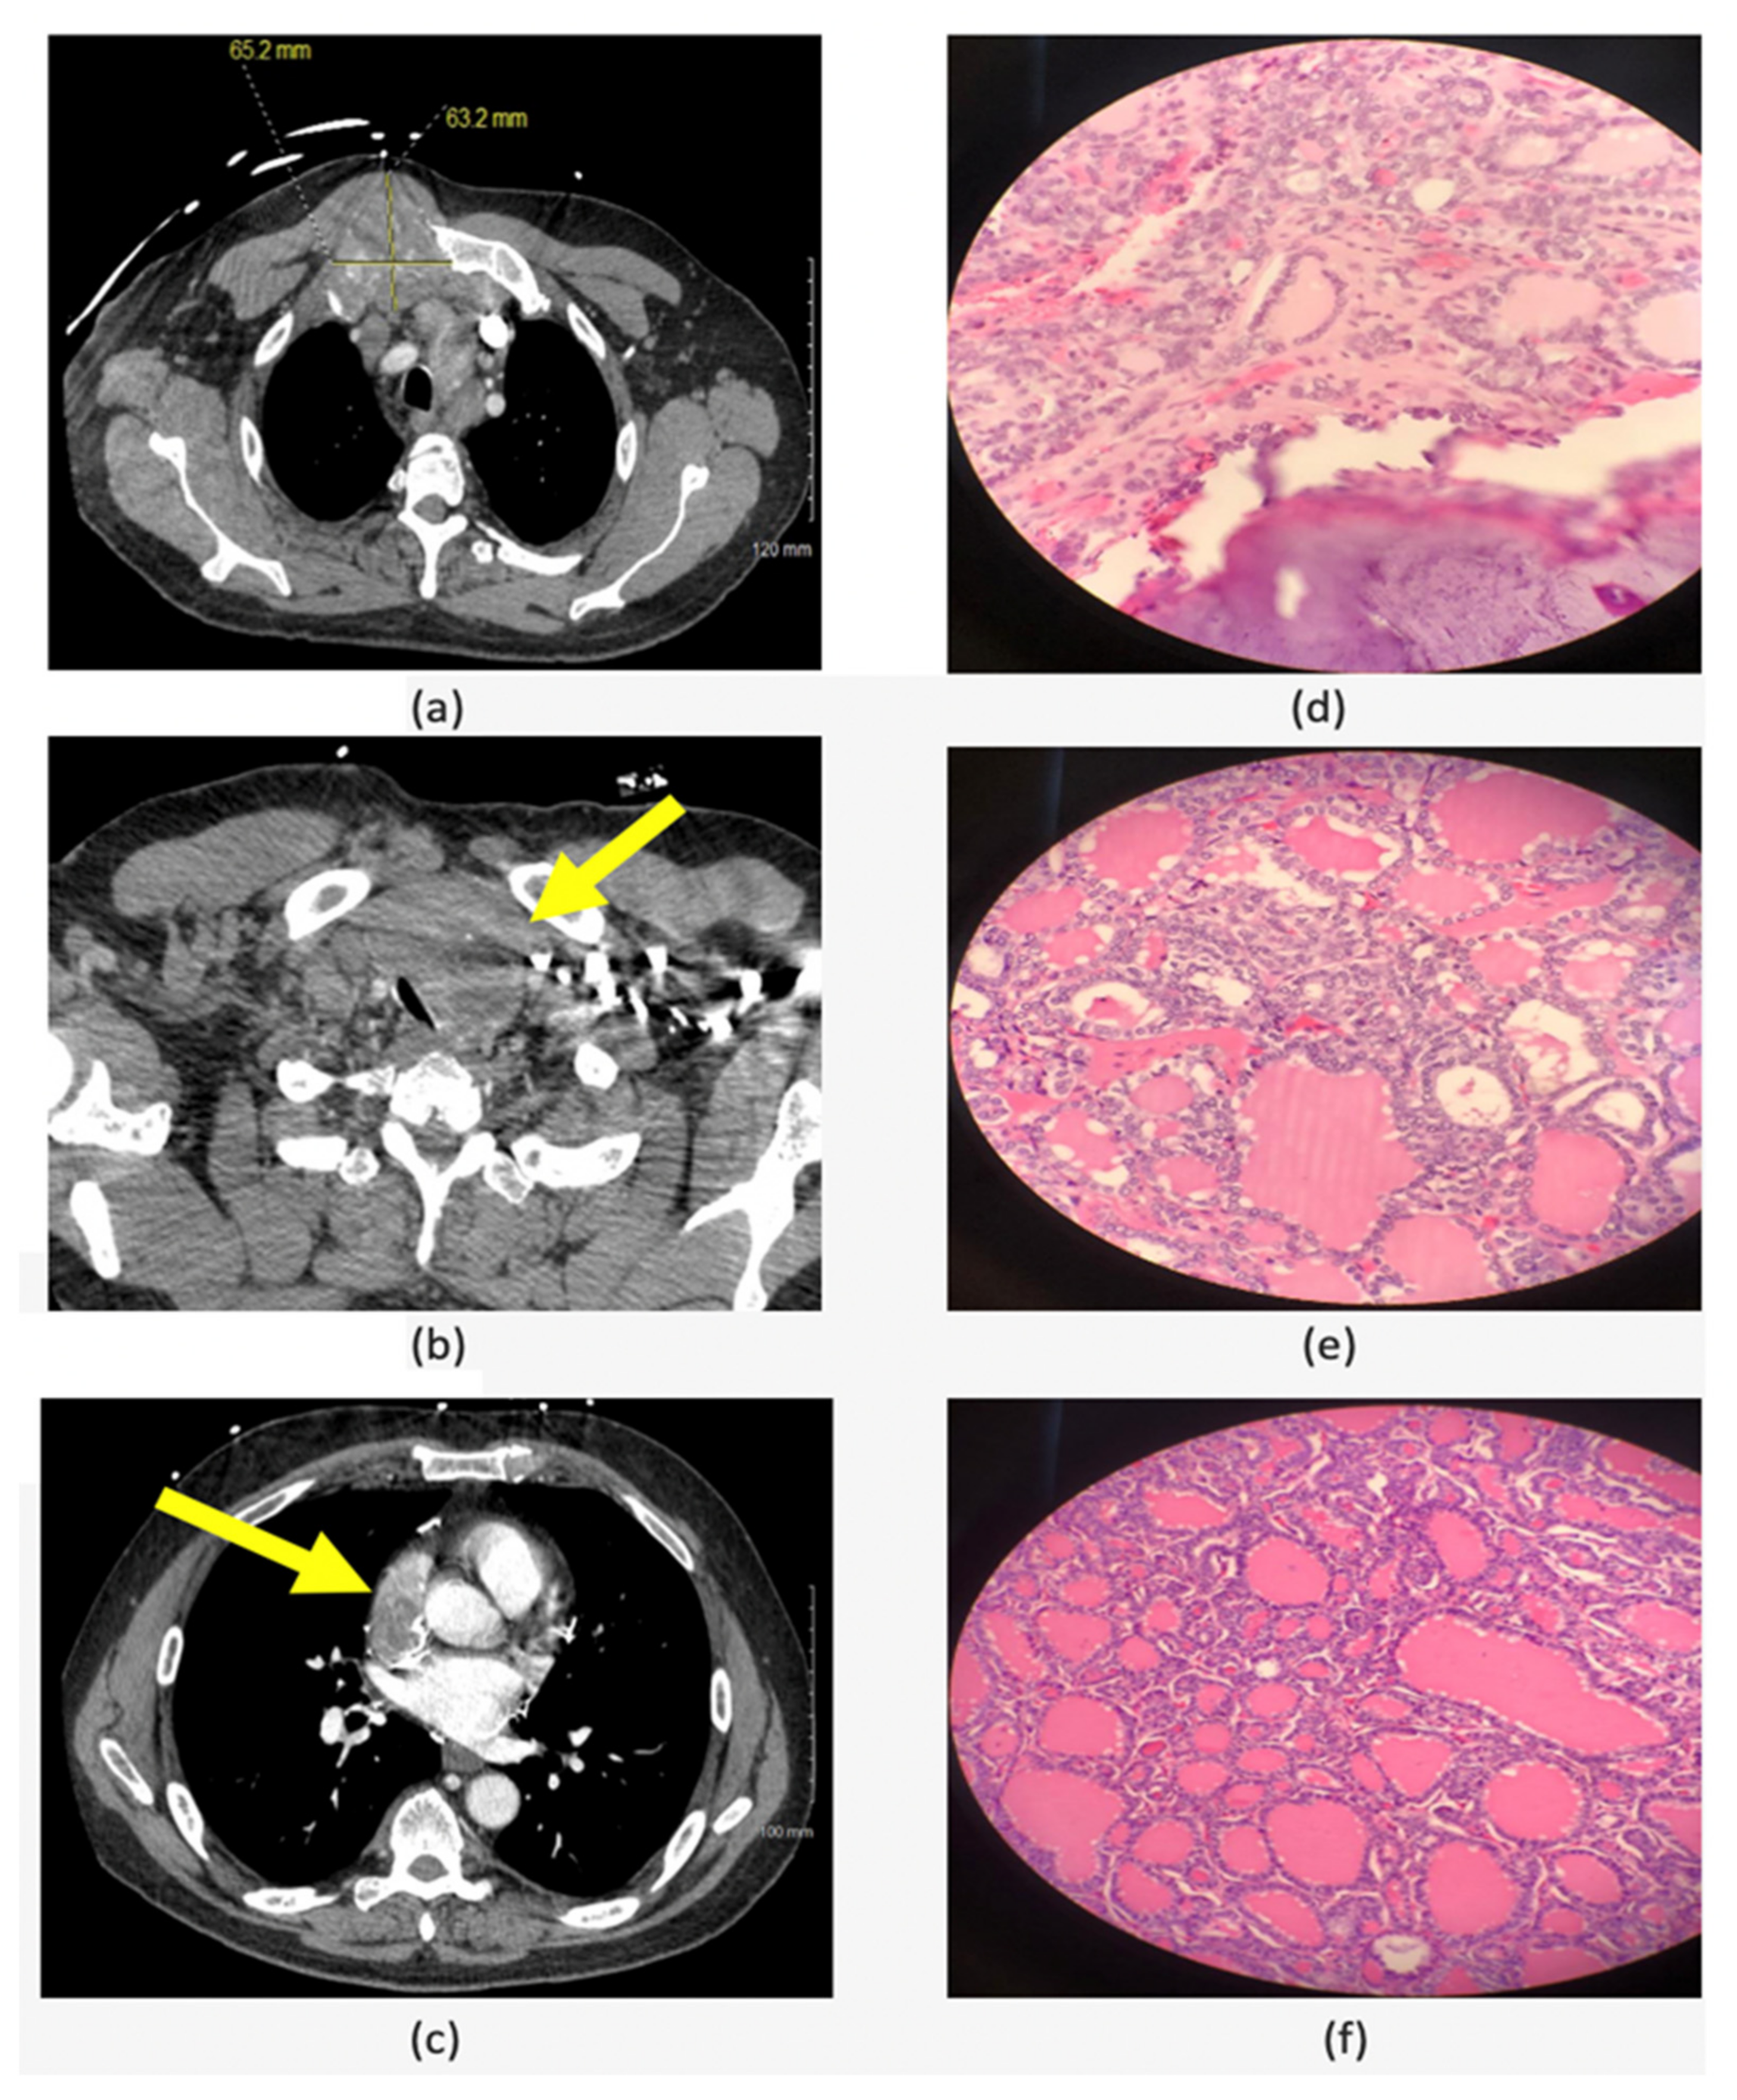

The criteria to define advanced thyroid cancer and the indications for systemic targeted treatment have been discussed in details in the American Head and Neck Society Endocrine Surgery Section and International Thyroid Oncology Group consensus statement on mutational testing in thyroid cancer: Defining advanced thyroid cancer and its targeted treatment [50]. The main goal for molecular testing in advanced thyroid cancer and anaplastic thyroid cancer is to detect targetable alterations and identify the optimal treatment for these patients [84]. After doing the molecular testing, multikinase inhibitors or systemic treatment targeting certain alterations (e.g., immune checkpoint inhibitors) can be given to the patients with progressing or symptomatic advanced differentiated thyroid cancer who had failed traditional therapy as neoadjuvant treatment in the presence of pre-operative advanced local disease [50] and as adjuvant therapy for selected patients with ATC [84]. One of the advanced thyroid cancer cases that was treated in our center is a 53-year-old male patient who presented with chest pain and chest wall mass. CT scan showed 6.5 cm right manubrial costal junction mass, 5.1 cm superior vena cava (SVC)/right arterial mass and left thyroid lobe mass (Figure 3). The biopsy of the chest wall was consistent with metastatic well-differentiated thyroid carcinoma and the thyroid USFNA showed PTC. Molecular testing (ThyroSeq v3) was positive for NRAS and TERT promoter mutations. According to the literature, the prognosis of cardiac metastasis from thyroid carcinoma is extremely poor [85]. However, since tumors with combined NRAS and TERT promoter mutations are not expected to cause local tissue invasion and are, therefore, potentially resectable, it was decided to proceed with surgical resection, followed by external beam radiation and RAI treatment. Final pathology from all the resected sites (thyroid, right atrium, SVC and chest wall tumors) was positive for FVPTC (Figure 3). Currently (23 months after surgery), the patient is doing well and had a partial response to the radiotherapy and three 150 mCi doses of RAI treatment with minimal progression of the bone metastasis. This case exemplifies that identifying molecular markers in advanced thyroid cancer can also play a role in the surgical decision in addition to detecting a possible targetable alteration/mutation.